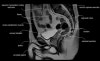

- Coronal section

T1 Allows for evaluation of both hips simultaneously even though the patient may be symptomatic in only one hip.

T2 allows for detection of abnormal fluid in both hips which may be seen in avascular necrosis, stress fractures, muscle tears or perilabral cysts.